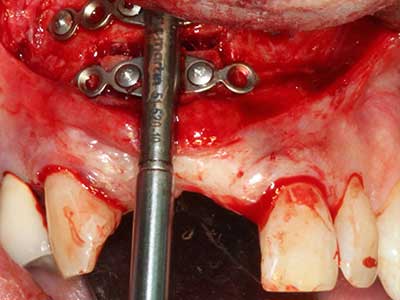

When surgical procedures are performed on bone in the immediate vicinity of sensitive structures such as blood vessels or nerves, rotary instruments pose a significant risk of iatrogenic injury. Piezoelectric devices can be helpful for preparation of bone covers and removal of hard tissue close to nerves, particularly for exposure of nerves after iatrogenic injury but also during nerve lateralization for resective and reconstructive procedures or implant placement (Fig. 17-20). Light contact between the piezotip and the nerve does not generally result in damage but proceeding incautiously with saw-like motions or attachments where a residual bone substrate remains may cause temporary or even permanent nerve damage. However, the risk of damage is considered to be substantially lower than when using saws or milling instruments (Pereira, Gealh et al. 2014).

Fig. 18: Preparation of a cortical cover with the piezo bone saw (Piezomed, W&H).

Fig. 19: Surgical site after neurolysis and removal of osteoma.

Fig. 20: The removed bone cover is re-adapted and fixed with an osteosynthesis screw (KLS Martin, Tuttlingen).